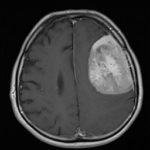

Cette masse peut entrainer notamment :

- Une irritation du cerveau qui se manifeste par une épilepsie

- Une compression voire destruction d’une partie du cerveau causant un affaiblissement ou une perte d’une fonction du cerveau

- Une augmentation de la pression à l’intérieur du crâne (espace inextensible à l’intérieur duquel vient s’ajouter le volume de la tumeur), ce qui va se manifester initialement par des maux de tête d’aggravation progressive qui vont s’associer à des nausées, des vomissements, des troubles visuels… Cet état peut aboutir à la perte de la vue dans les formes d’évolution lente et au décès dans les formes d’évolution rapide.